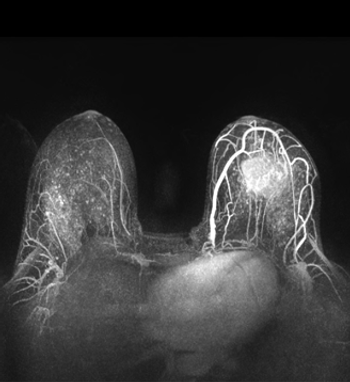

A new study found that magnetic resonance imaging (MRI) screening improved the detection of small, high-grade breast cancers in women with average risk.

Expert radiologists were able to screen magnetic resonance images and rule out breast cancer diagnosis with a negative predictive value of about 99% using an abridged breast MRI protocol in a single-center study presented Saturday at the ASCO Breast Cancer Symposium 2013.